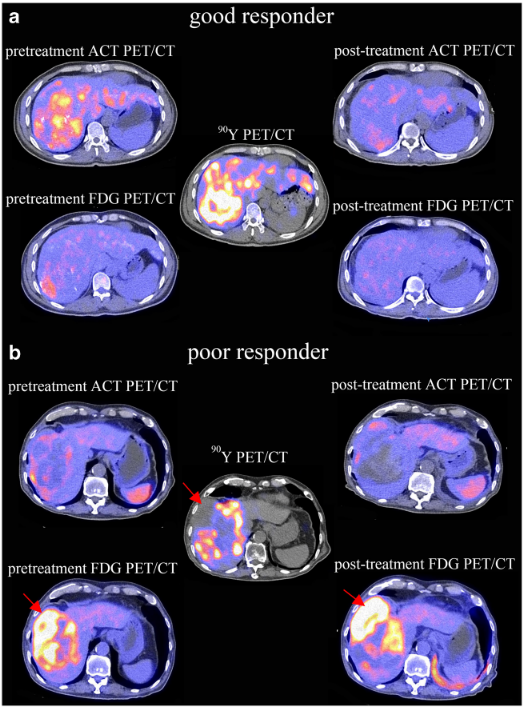

C-11 ACT, F-18 FDG PET/CT and Y-90 microsphere radionuclide therapy

In the same HCC, C-11 ACT and F-18 FDG can be taken up by different parts of the same tumor due to different cellular differentiation